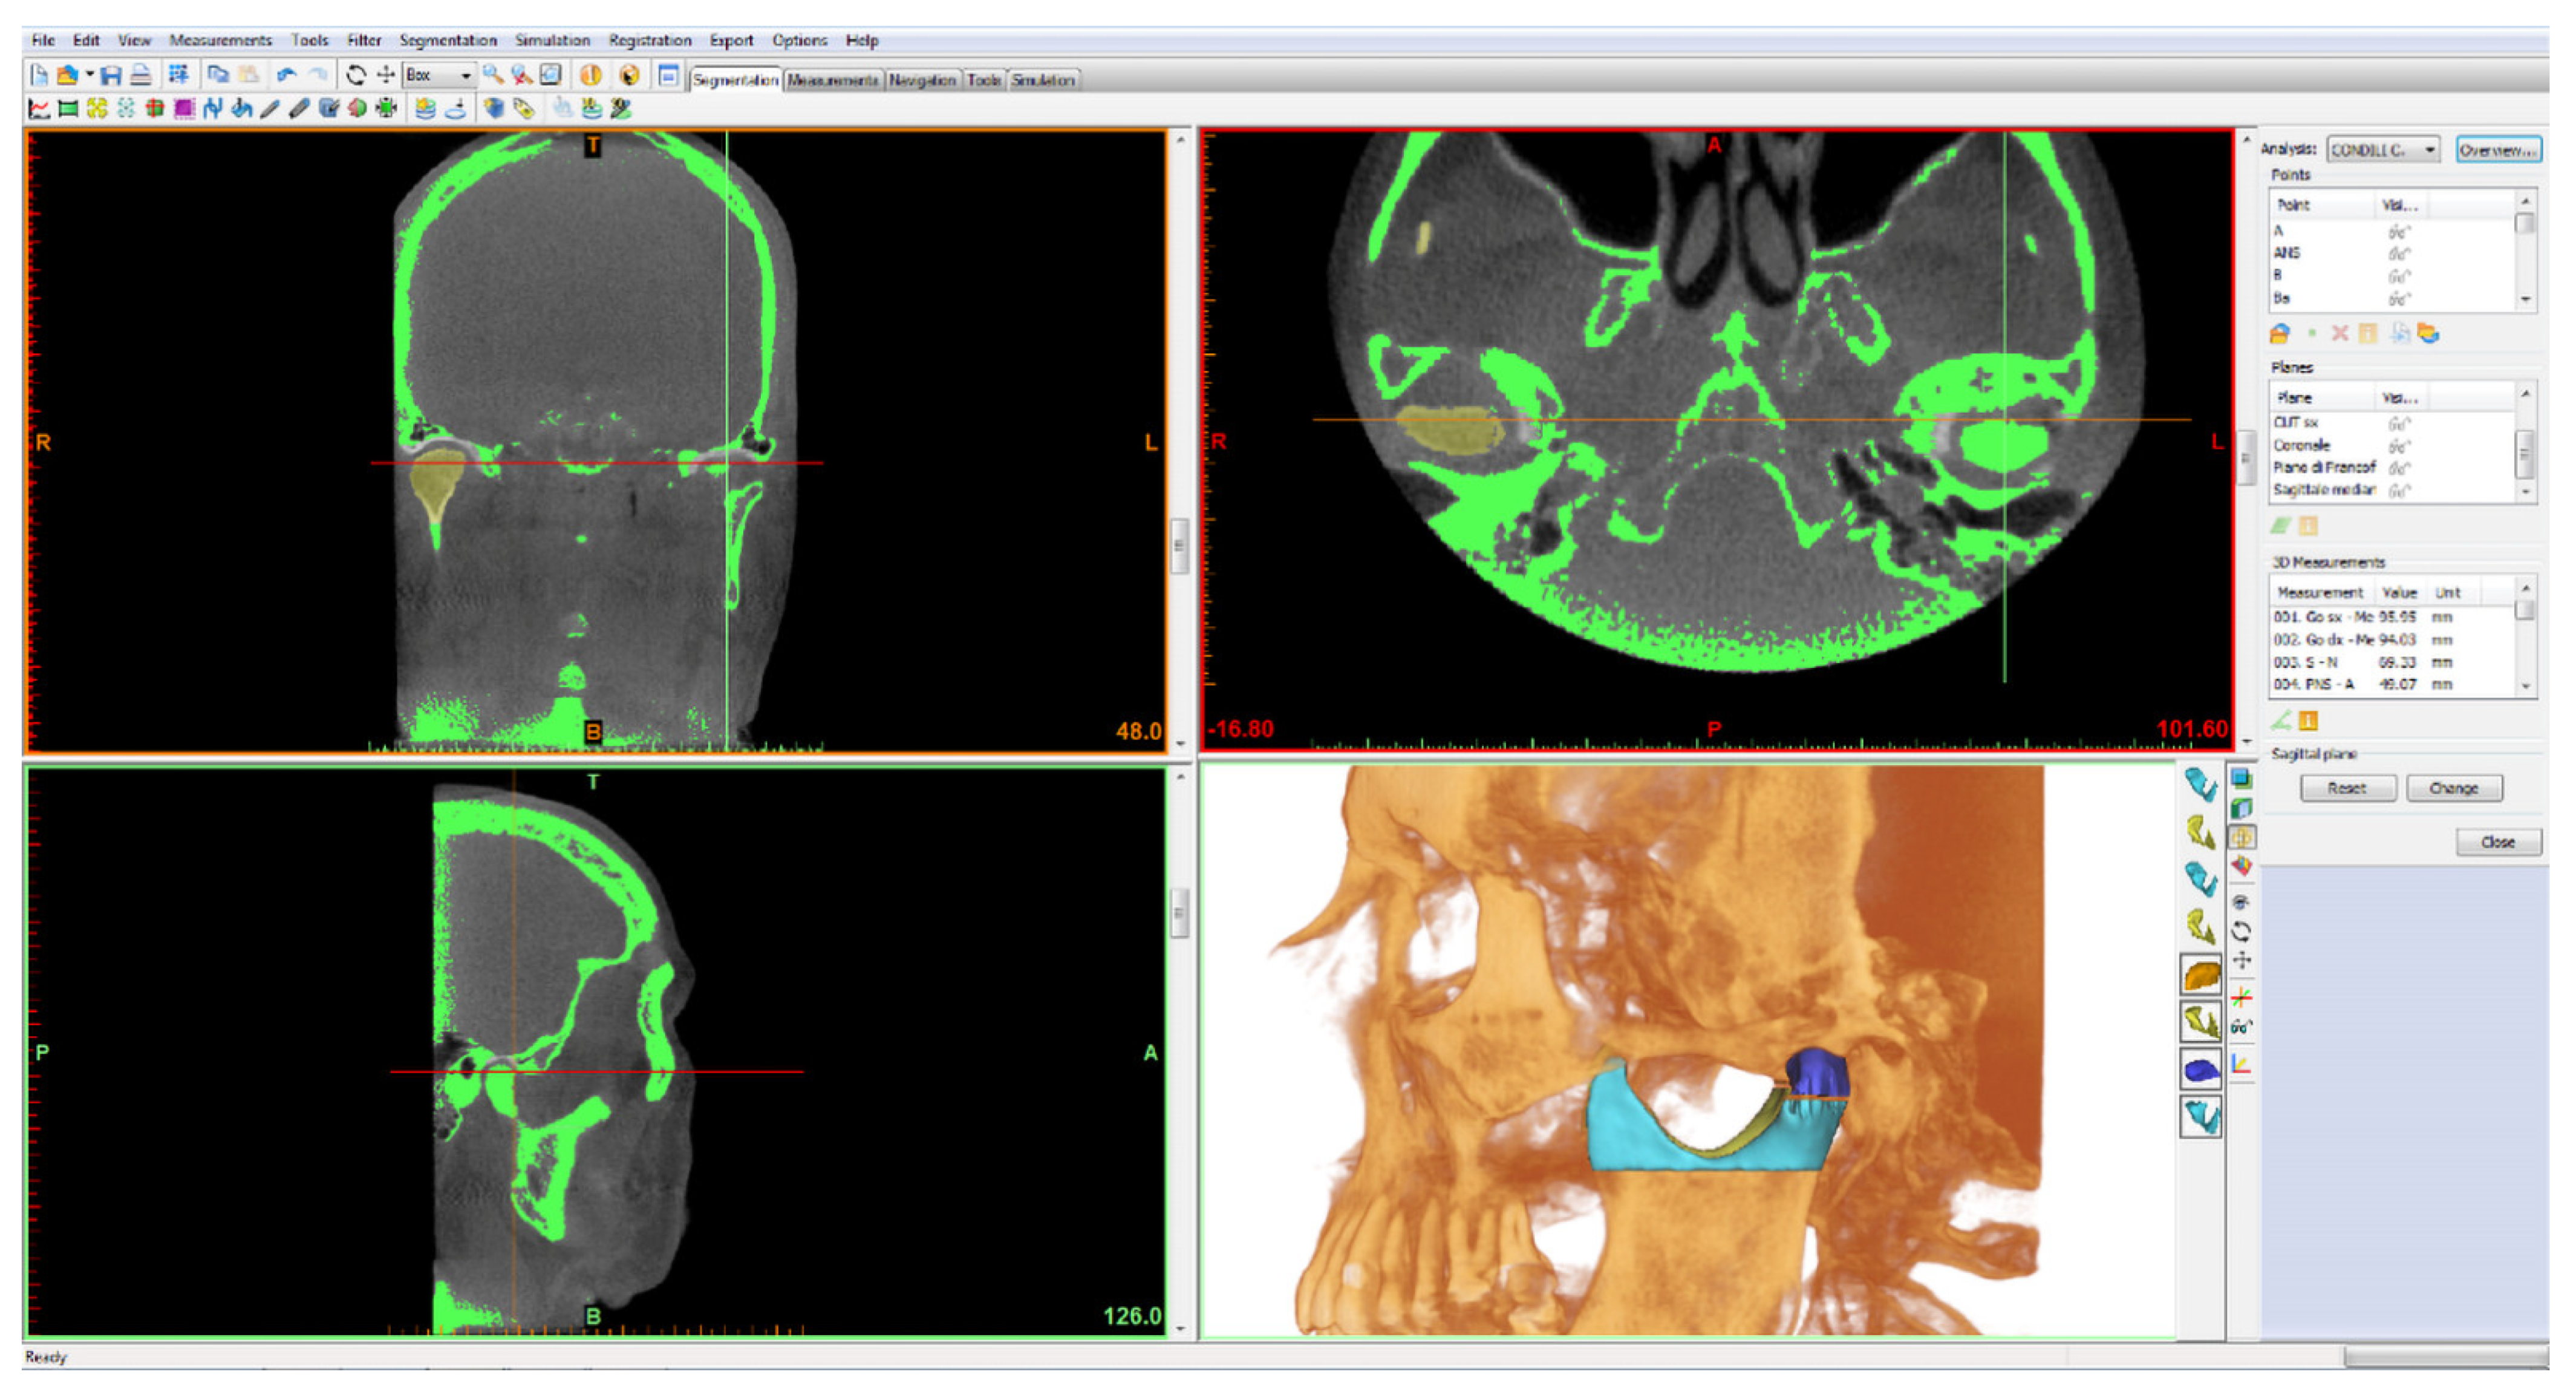

2.1. Mandibular Condylar Segmentation and Volume

- Pterygoid fovea point (right/left FP): most recessed point on the front face of the mandibular neck, identifiable in the three projections: axial, coronal and sagittal. It was chosen as the point that delimits the separation passage between the head and neck of the mandibular condyle.

- Frankfurt plane: calculated as the plane passing through the lower right and left orbital points (right/left OR) and from the right and left porion points (right/left Po);

- Cut plane of the right condyle (right CUT): plane passing through right FP and parallel to the Frankfurt plane;

- Cut plane of the left condyle (left CUT): plane passing through left FP and parallel to the Frankfurt plane.